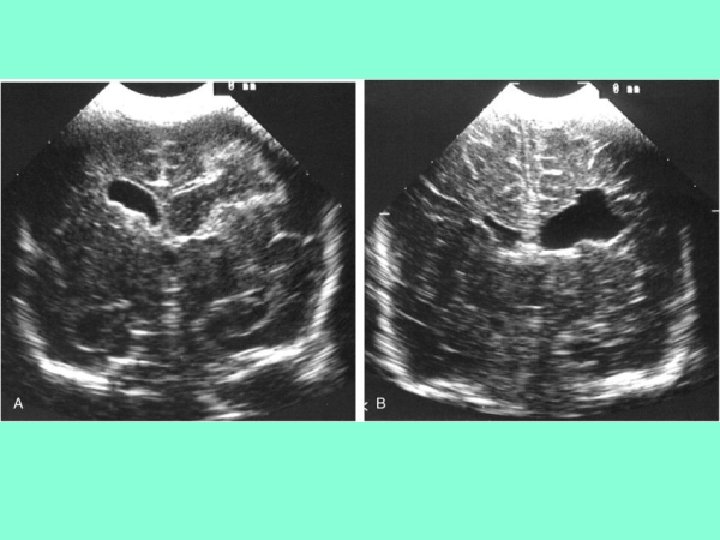

Классификация ПВЛМ From De. Vries L et al: The spectrum of leukomalacia using cranial ultrasound. Behav Brain Res 49: 1, 1992. • 1 степень – транзиторное перивентрикулярное увеличение эхоплотности в первые 7 дней жизни • 2 степени –локальные лобно-височные кисты • 3 степени - распространенные перивентрикулярные кисты • 4 степень – распространенные перивентрикулярные и субкортикальные кисты

• А – нормальный ребенок в 31 неделю ГВ • В и С - бивентрикулярные кисты